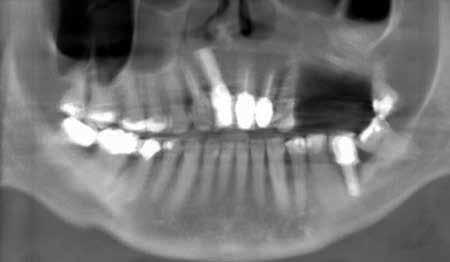

Magnetic resonance imaging (MRI) has been a staple in medicine and dentistry for many years. In dentistry, it serves a somewhat confined role in imaging the temporomandibular joints (TMJ) and occasionally the head and neck, including cysts or tumors. Dental MRI research and publications on these indications, as well as more “traditional” dental imaging tasks such as caries or periapical lesion detection, have progressed steadily since the mid-1980s, followed by a rapid increase in published papers in the early 2020s. These studies have long demonstrated the utility of MRI TMJ and cyst/tumor imaging, as well as the promise of MRI for essentially the entire range of dental imaging indications. Indications include caries, periapical disease, periodontal disease, growth and development/

The newly formed Orofacial MRI Center (OMRIC, dentistry.umn.edu/omric) at the University of Minnesota School of Dentistry is home to the first dental-dedicated MRI (ddMRI) unit in North America and the second installation of its kind in the world. Researchers Drs. Don Nixdorf and Laurence Gaalaas have an extensive track record in dental MRI research and development. Still, they are thrilled to have as an imaging tool one of the very first dental-dedicated MRI units, a Siemens MAGNETOM Free.

Max Dental Edition* MRI scanner. In collaboration with Dentsply Sirona and Siemens Healthineers, Nixdorf and Gaalaas secured a multi-year research agreement and constructed a physical imaging center around a Free.Max MRI unit. Beginning in early 2025, they initiated research studies to investigate the utility of ddMRI diagnosis in patients with endodontic, orthodontic and TMJ conditions. Such work will establish the utility of an experimental dedicated extraoral dental MRI coil and support proven indications for ddMRI imaging in endodontic, orthodontic, TMJ and other dental patient populations.

While most dentists are likely familiar with the basics of how information is displayed on an MRI image, the adoption of ddMRI will require a mindset shift for virtually all dental team members who may utilize this new technology in their respective clinics. First, the grayscale is fundamentally different from that used for all X-raybased imaging. In MRI, soft tissues are commonly displayed as gray or bright white signals, while hard tissues, such as teeth and bone, are shown as very dark gray or black signals; air remains black. Furthermore, MRI offers the option to select from a variety of different sequences, each of which can produce a slightly different tissue grayscale and corresponding image. Some sequences, such as T1 or PD, do an excellent job of demonstrating detailed anatomical relationships. Other sequences, such as T2, do an excellent job of demonstrating the presence of fluid accumulation within tissues. Many available “Fat sat” or “STIR” sequences may selectively “zero out”, “suppress”, or “saturate” the signal of fat, which is traditionally very bright white on MRI images, to reveal the otherwise hidden signal from subtle fluid accumulation or inflammatory changes. Some of these specialized sequences may not accurately depict anatomic relationships, but are designed to be exceptionally sensitive to detecting inflammatory changes with a bright signal. The short T2 sequences mentioned above are beginning to depict the hard tissue differences between cortical bone and medullary bone, as well as the differences between tooth dentin and enamel. Developing, learning and using all these different sequence choices in concert is where the real research and diagnostic potential of ddMRI lies. t

Proton density image of horizontally impacted tooth #17.

Proton density image of TMJ demonstrating anterior disc displacement, disc fold and joint effusion.